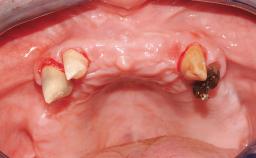

Case Type Edentulous Maxilla

Soft Tissue Anatomy Intact Defective

Bone Volume Horizontally and vertically sufficient Horizontally deficient Deficient vertically or deficient vertically AND horizontally

Soft Tissue Contour and Volume Slightly compromised